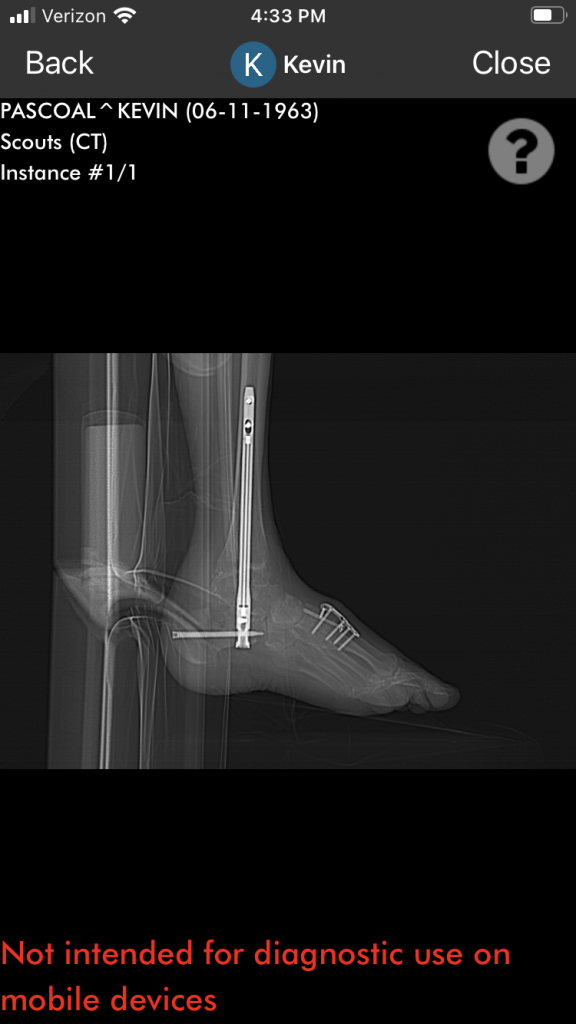

After 31 years in law enforcement, I retired and began a new career in school security. During my police career I sustained several injuries to my ankle, which began to worsen as the years passed. Ultimately in 2019, I had a full ankle collapse, which was so severe that I was actually walking on top of the side of my foot.

Upon consulting with Dr. Fragomen, he immediately reassured me that this condition could be corrected with an ankle fusion and complete healing within 6 months. As you hear the words ankle fusion you think the worst - permanent limp, limited mobility, and a failed fusion runs through your mind.

Having no other choice, fusion surgery was completed in June 2022. After a four-hour surgery done by Dr. Fragomen and Dr. Ellis, it was a complete success.